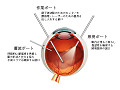

手術と処置 硝子体失血手術と白内障手術を受ける

硝子体失血手術

硝子体失血手術の様子 ネットでこの写真を見てゾッとなる

白内障手術 白内障は日帰り手術と聞き簡単と思っていたが、結構凄い手術だと知る